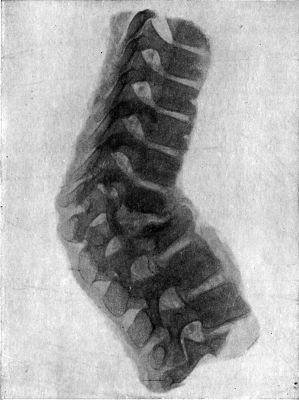

207.Compression Fracture of Bodies of Third and Fourth Lumbar Vertebræ426

208.Fracture-Dislocation of Ninth Thoracic Vertebra428